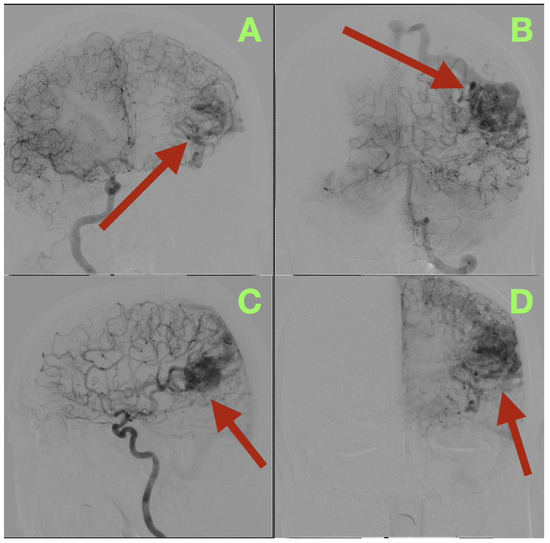

Background/Objectives: Arteriovenous malformations (AVMs) in the dominant temporo-parieto-occipital (TPO) junction of the brain are extremely rare and very difficult to remove surgically because this area includes multiple sensory and language networks. Due to the fact that many patients present with bleeding, surgeons have to find a delicate balance between removing all of the AVM tissue and preserving the functional areas of the brain where important functions occur. This study is reporting a case demonstrating how precise clinical–radiologic correlation, detailed anatomical knowledge, and deliberate microsurgical techniques can allow safe removal of the AVM and improve the patient’s neurologic function without the need for additional intraoperative technology. Case Presentation: A 47-year-old right-handed male patient experienced persistent neurological deficits after experiencing a hemorrhage from an AVM in his dominant posterior hemisphere, which included mild language difficulties, right hemifacial–brachial spasticity, parietal sensory loss and a visual field defect of his right eye known as an inferior quadrantanopia localized to the TPO junction. Cerebral angiography identified a small, compact, high-flow AVM (40 × 30 mm) fed by distal branches of the middle cerebral artery (M4), posterior cerebral artery (P4), anterior cerebral artery (A4), as well as a small branch of the superior cerebellar artery (SCA). Blood drained into two veins of the Trolard and Labbé. The authors removed the AVM completely by circumferential dissection of the nidus along gliotic planes using a microscope. Feeders were then sequentially disconnected, and the venous outflow was preserved until the AVM could be removed en bloc. Post-operative angiograms demonstrated complete removal of the AVM with normalization of blood flow to the surrounding cortex. The patient’s neurologic function improved over time and at three months post-operatively, he was functioning independently (modified Rankin Scale = 1; Barthel Index = 100) and there was no evidence of residual nidus or edema on imaging. Conclusions: High-flow AVMs in the dominant TPO junction can be completely removed using a disciplined microsurgical approach and a feeder first/vein last disconnection method based on anatomy. The patient’s improvement in function represented reperfusion and reintegration of an injured but still functional network of the brain, reinforcing the idea that careful observation, a deep understanding of brain anatomy, and restrained surgical technique are critical to achieving long-term results in AVM surgery. Full article

Figure 1